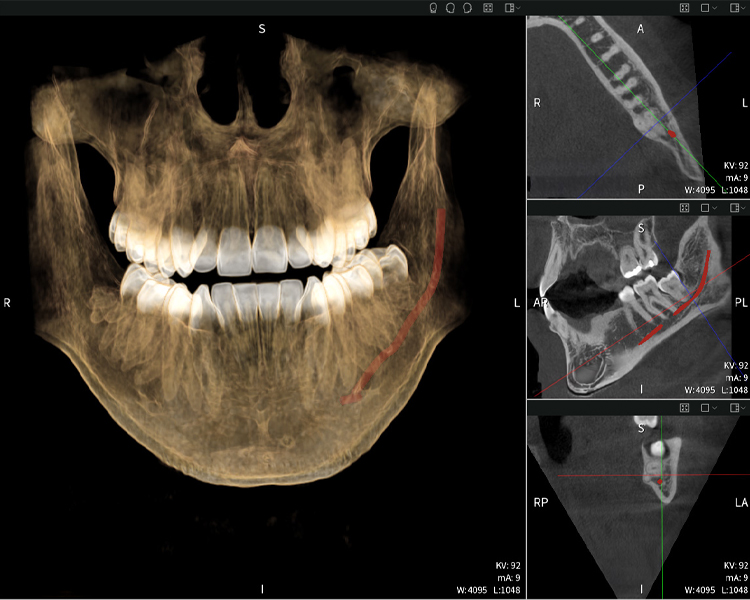

Nachstehend finden Sie einen Fall von Dr. med. dent. Oliver A. Centrella, in dem die CBCT-Aufnahmen mit Seethrough Max entscheidende Informationen zur komplexen Anatomie sowie zur kritischen Beziehung zwischen den Weisheitszähnen und dem Nervus alveolaris inferior lieferten. Bei diesem Fall besteht eine Indikation zur chirurgischen Entfernung der Weisheitszähne.

Abbildung a

- Oben links: Axiale Schnittansicht des linken Unterkiefers (Region 38) mit Darstellung des Nervus alveolaris inferior (rot) in unmittelbarer Nähe zu den Wurzeln des Zahns 38.

- Oben rechts: 3D-Rekonstruktion des gesamten Unterkiefers zur Orientierung. Der rot markierte Nervus alveolaris inferior verdeutlicht seine Lage im Kieferknochen.

- Unten links: Sagittale Ansicht des Unterkiefers (Region 38), die die enge räumliche Beziehung zwischen den Wurzeln und dem Nervenkanal verdeutlicht.

- Unten rechts: Koronale Ansicht des Unterkiefers (Region 38) entscheidend für die Beurteilung der räumlichen Lage der Wurzeln zum Nerven.

Abbildungen b–d zeigen verschiedene Ansichten einer 3D-Rekonstruktion des Unterkiefers und bieten eine umfassende Übersicht über die Anatomie des Unterkiefers, die Lage der Nerven im Verhältnis zu den Zähnen und ermöglichen die Beurteilung der Zahnsymmetrie und Ausrichtung.

Abbildung d zeigt den bereits vorbehandelte Zahn 48, dessen Krone entfernt wurde und dessen Wurzeln nahe am Nerv belassen wurden, was das hohe Risiko einer Nervenschädigung verdeutlicht.